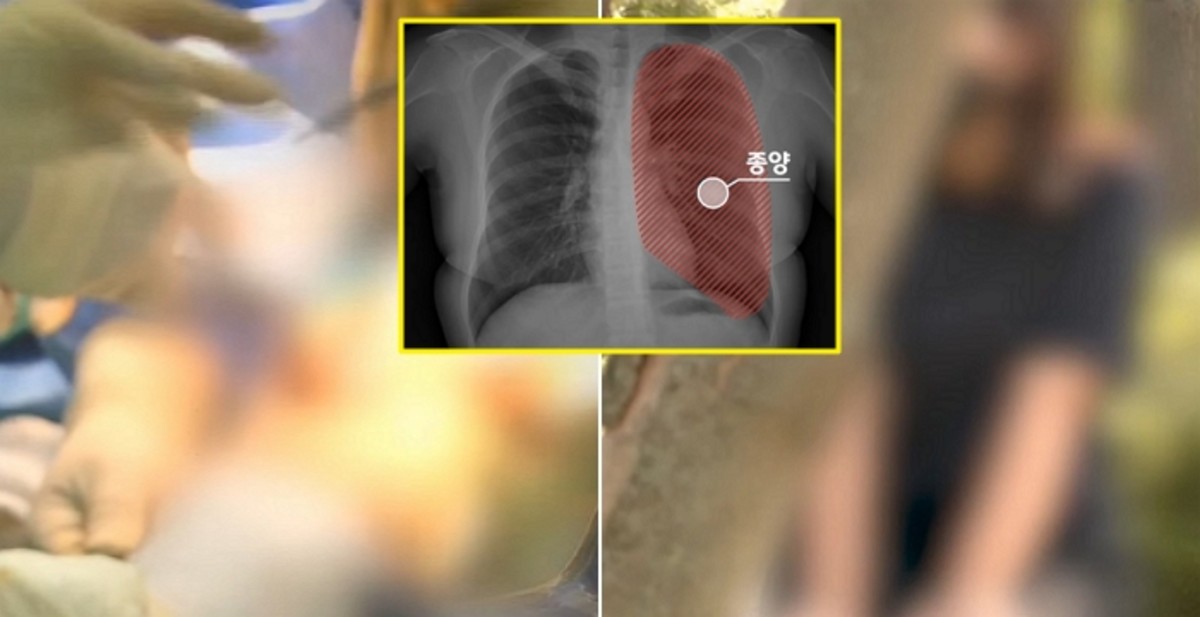

앞서 A씨는 4년 전 왼쪽 폐에서 2센티미터짜리 종양을 발견했다. 검사 결과 폐암 1기였고 폐암 수술 명의로 불리는 유명 병원의 조모 교수에게 수술을 받았다.

그러나 한 달 뒤 경과를 확인하려 CT를 찍었다가 당황스러운 말을 듣게 됐다. 수술 중 중양이 있는 왼쪽 폐 아래쪽을 잘라낸 것이 아닌 멀쩡한 윗부분을 잘라낸 것이다.

뒤늦게 원래 종양 부위를 다시 잘라내니 왼쪽 폐 전체가 사라졌고 A씨는 결국 오른쪽 폐로만 숨을 쉬게 됐다.